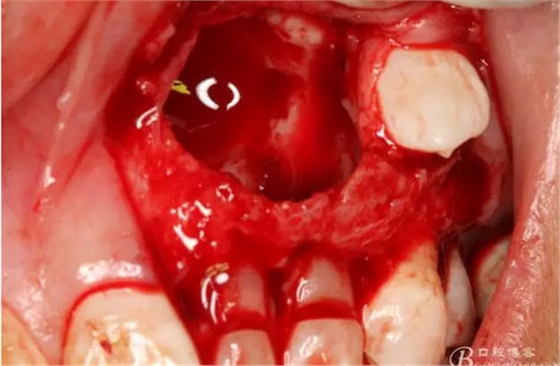

圖17.呼之欲出的巨大牙瘤組織。

圖18.摘除囊腫后遺留的巨大骨腔

圖19.生理鹽水沖洗骨腔,修整骨腔表面